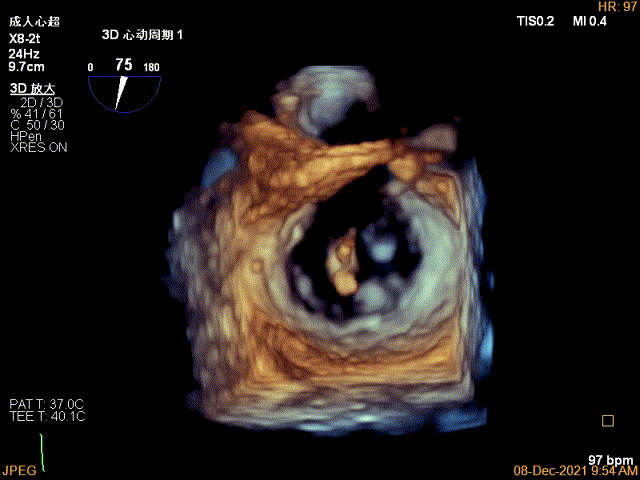

3D-VIEW验证结果

3D-Color-view验证残余分流位于外侧